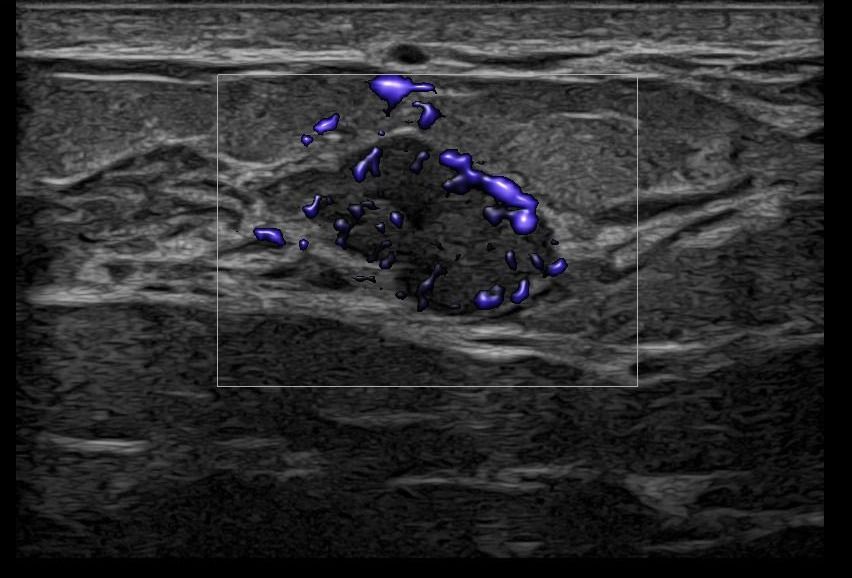

Elastography can highlight the elasticity of a lesion, indicating whether it is hard or soft. Through this technique, we can assess the nature of the lesion, providing indications of whether it is benign or malignant. Additionally, with the contribution of Color Power Doppler and B-Flow, we can monitor the vascular flow within the lesions, offering even more information about the type and nature of the abnormality.